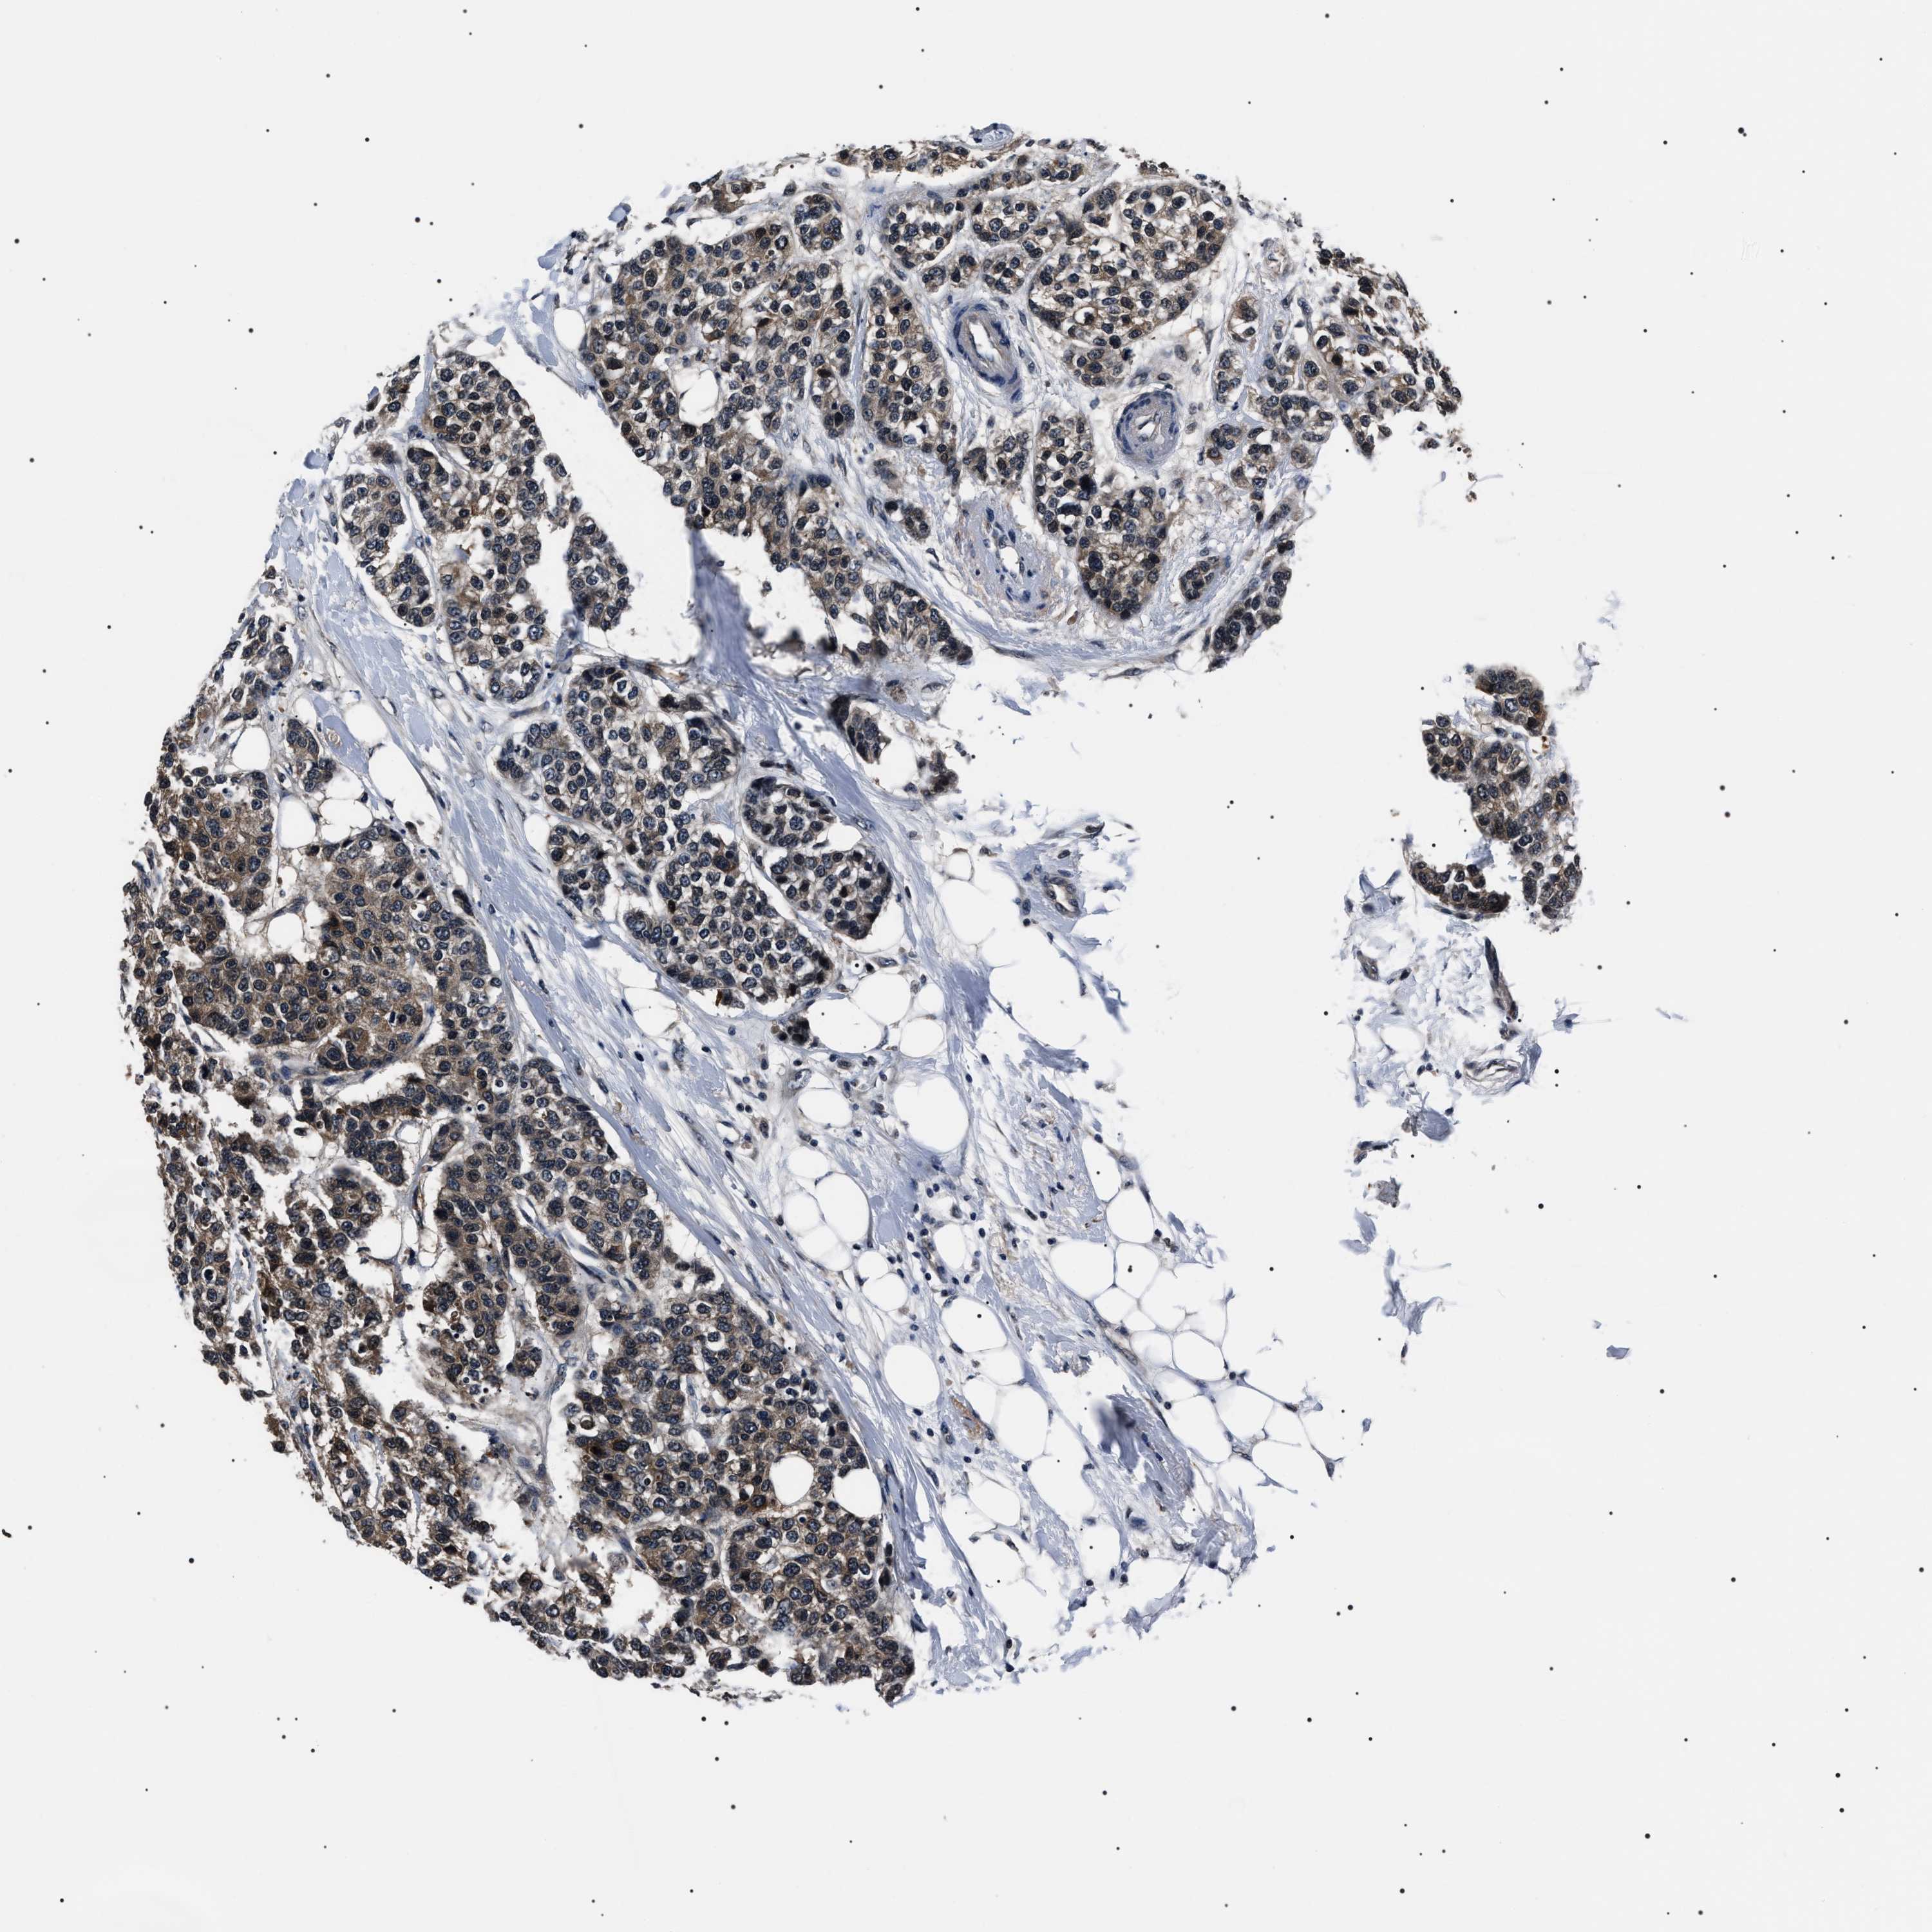

CANCER BREAST CANCER Show tissue menu

BRCA TCGA BRCA VALIDATION PROTEIN EXPRESSION